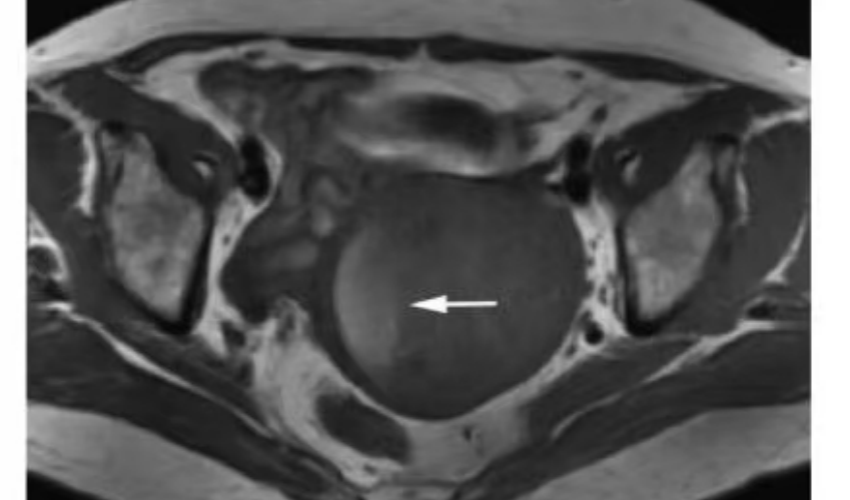

中晚期宫颈癌典型MRI表现